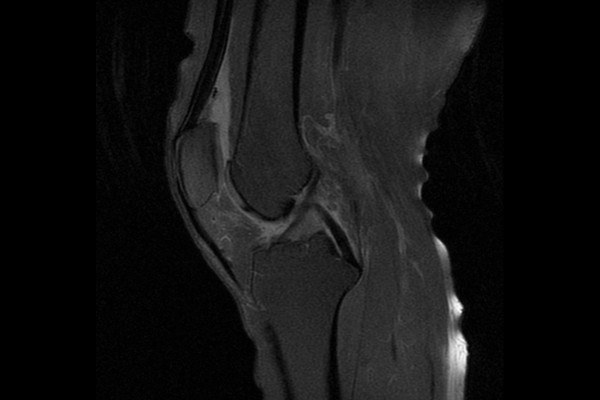

MRI 검사를 했을 때 역시 무릎 관절 내에 유리체(뼛조각)가 확인되어 무릎 관절 내 유리체(뼛조각)(Bony loose body knee Rt.)을 진단하였습니다.

통증이 지속되었기 때문에 수술적 치료인 관절경하 관절 내 유리체(뼛조각) 제거술(Rt. knee A/S (loose body removal))을 진행하기로 하였습니다.